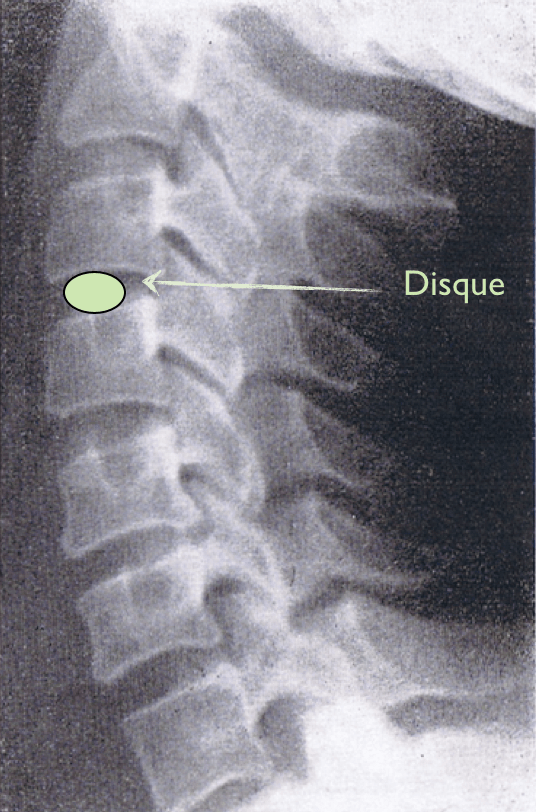

Cervicale. Disque normal Publié 4 octobre 2013 à 536 × 812 dans Les disques et vos douleurs Suivant → J’aime chargement… Poster un commentaire ou un rétrolien.